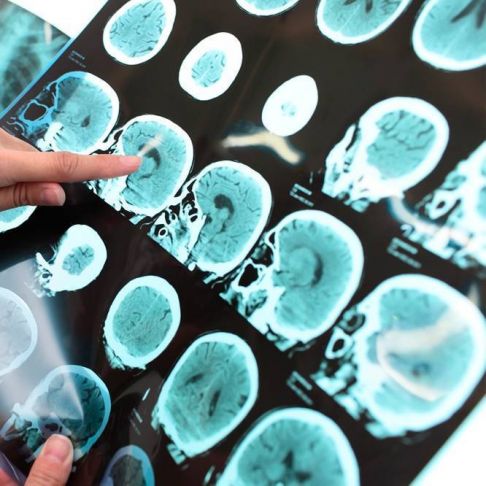

- Resonancia magnética en órganos: si el paciente posee una afección en algún órgano, una resonancia puede ayudar al médico a ver las áreas que están siendo afectadas. Puede ver órganos como corazón, pulmones, cerebro, hígado, páncreas y más.

PET: es la tomografía de emisión de positrones. Es un tipo de diagnóstico no invasivo que permite capturar imágenes de los órganos del cuerpo y mostrar la actividad que realiza. Esta prueba permite detectar algunos tipos de cáncer, linfomas y nódulos pulmonares.